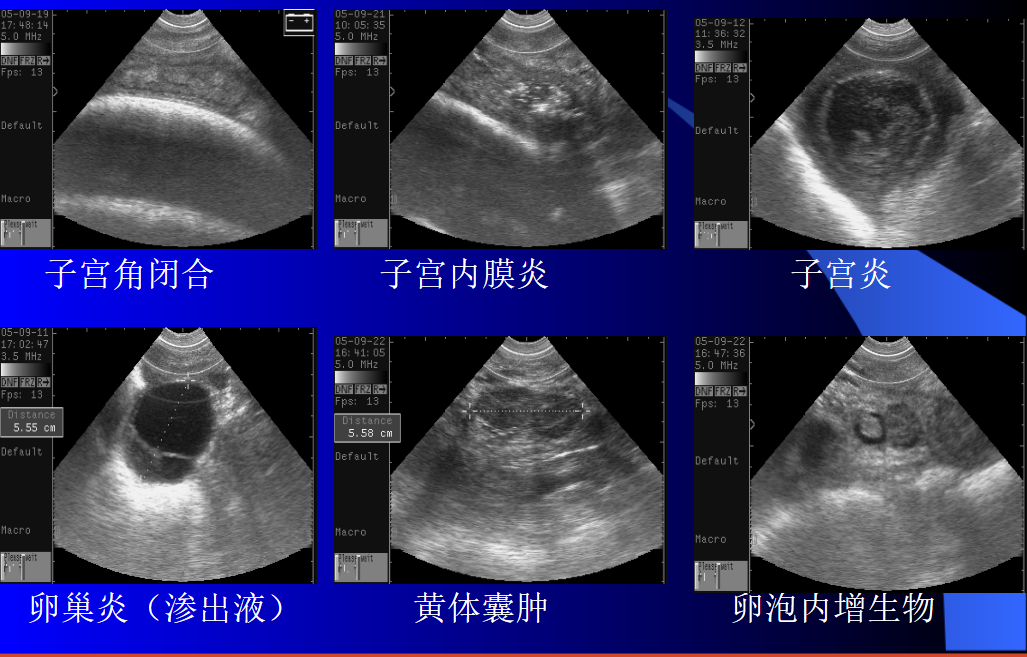

超声的实际应用包括妊娠状态的早期评估、怀双胎的母牛的识别、卵巢和子宫病变的检测以及胎儿性别的确定。这些应用中的每一个都为提高牛场的母牛繁殖效率提供了测试结果的准确性是,大多数兽医学生被教导超声波是牛繁殖工作的辅助技术。然而,超声成像的信息收集能力远远超过直肠触诊。从事母牛繁育的兽医老师和牛场技术老师使用超声波进行常规生殖检查的推广教学计划是该技术快速应用于母牛繁育行业的关键一步

经直肠实时超声在牛繁殖研究中的应用代表了一项技术突破,彻底改变了生殖生物学知识。通过超声成像产生的新研究信息阐明了牛复杂生殖过程的性质,包括卵巢卵泡动力学、黄体功能和胎儿发育。超声技术在母牛繁育的早期整合包括诸如经阴道卵泡抽吸和卵母细胞回收等应用,以及作为胚胎移植程序的补充技术